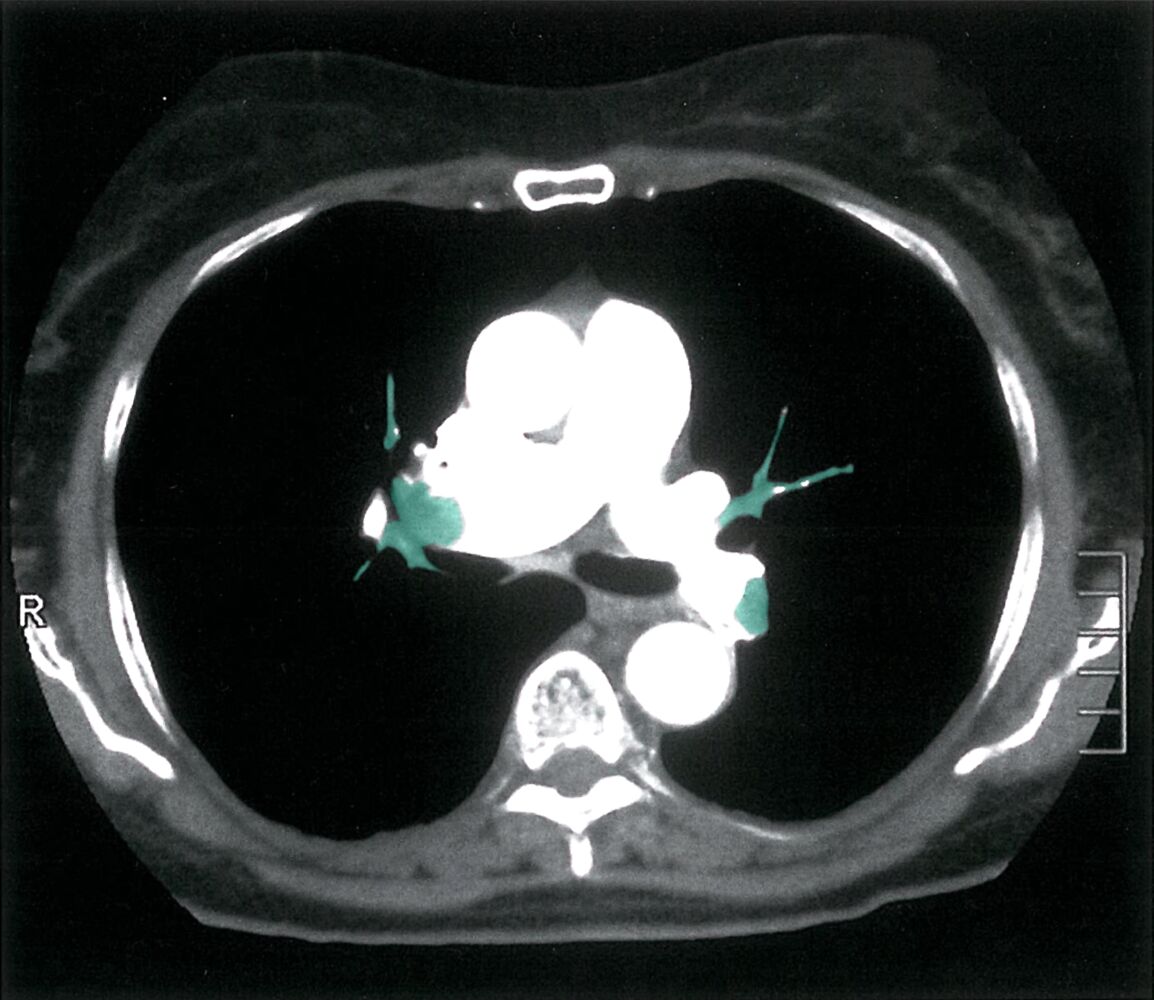

Lungenembolie - CT des Thorax (mit Kontrastmittel, pulmonalarterielle Phase, axialer Schnitt)

73-jährige Patientin mit starker Dyspnoe unklarer Genese; vor vier Tagen habe sie eine längere Busfahrt gemacht und beim Aussteigen plötzlich Luftnot verspürt

Grün: Deutliche Kontrastmittel-Aussparungen in den Pulmonalarterien und ihren Abgängen beidseits